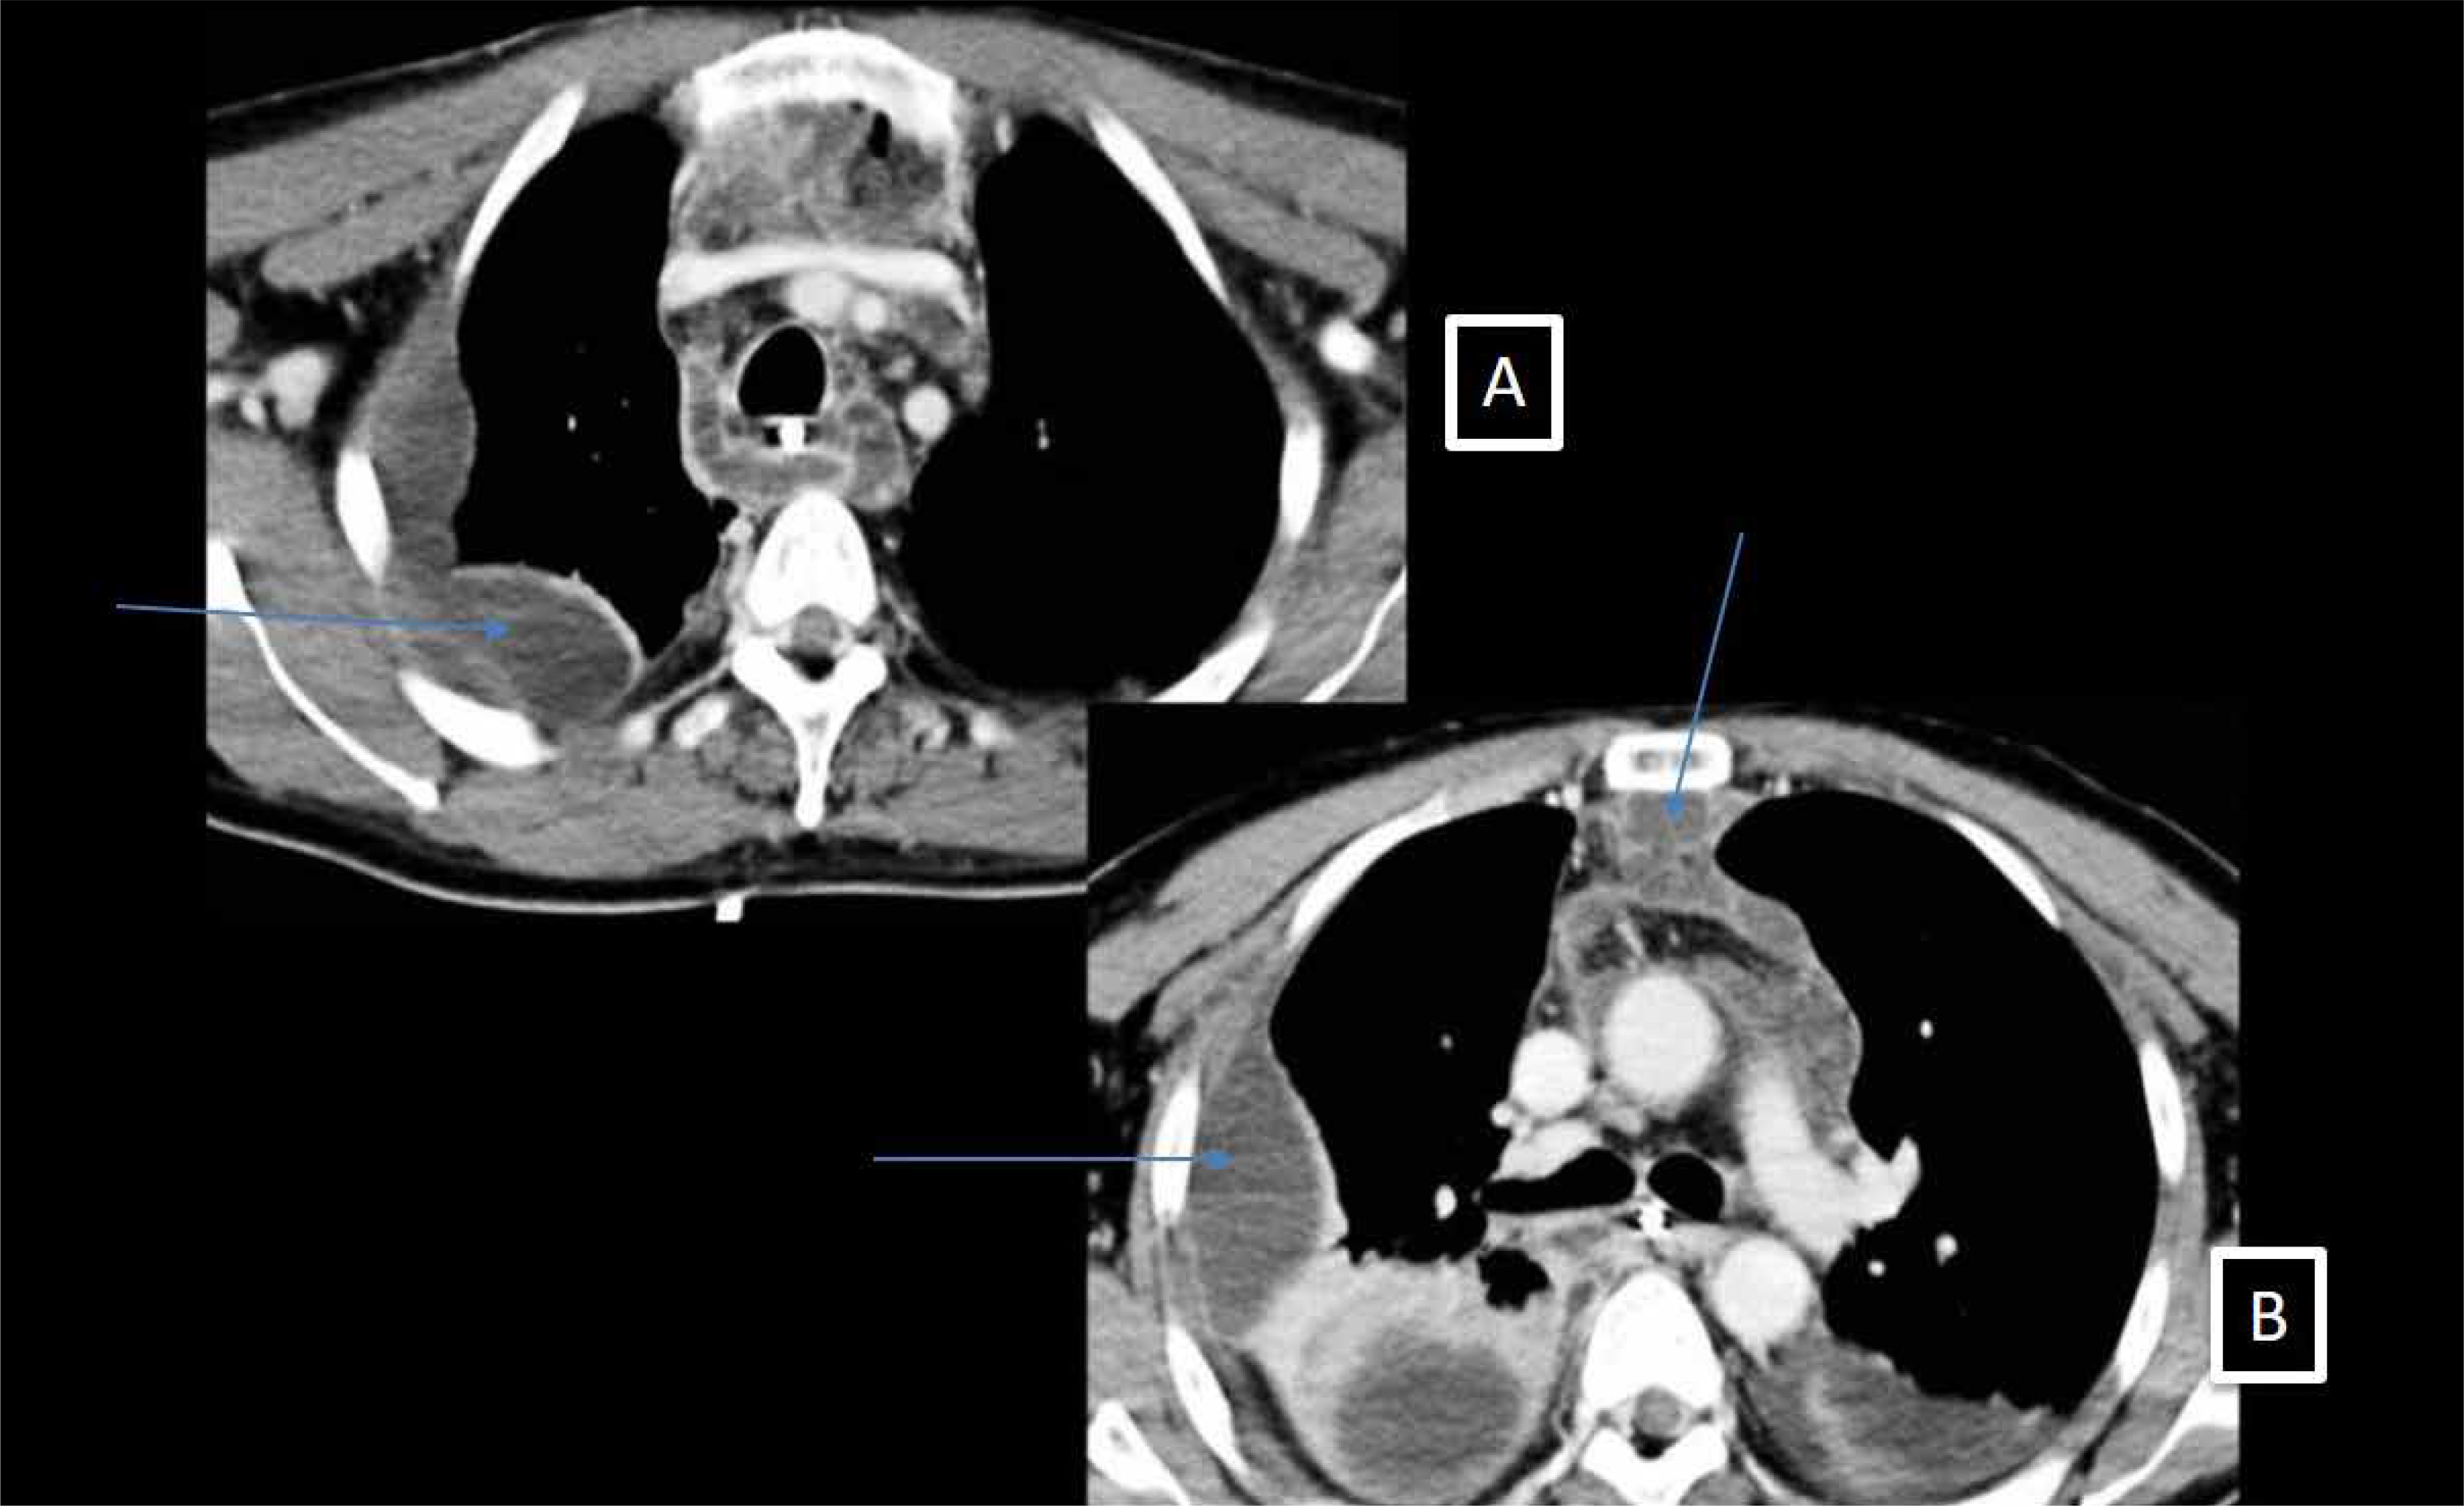

Figure 4

Perioperative view of a right anterior thoracotomy showing a huge collection in the anterior mediastinum